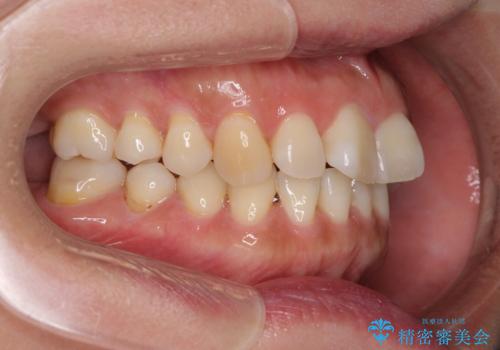

インビザライン・ライトは、製作できるアライナーの枚数に制限があるため、移動可能な量に限りがあります。

一方で、半年から1年程度で治療を終えることができるため、軽度の歯列不正の患者様には大変お勧めです。